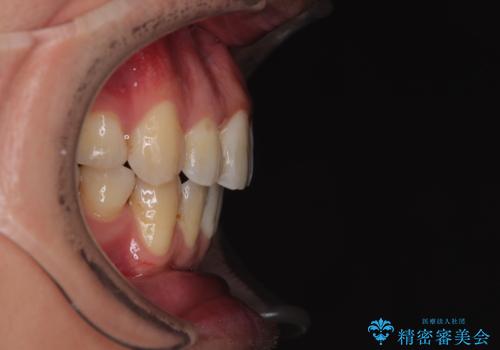

奥歯の噛み合わせがずれている「シザーズバイト」を適正に整えることで、見た目だけでなく機能性も向上し、安定した咬合が獲得できました。